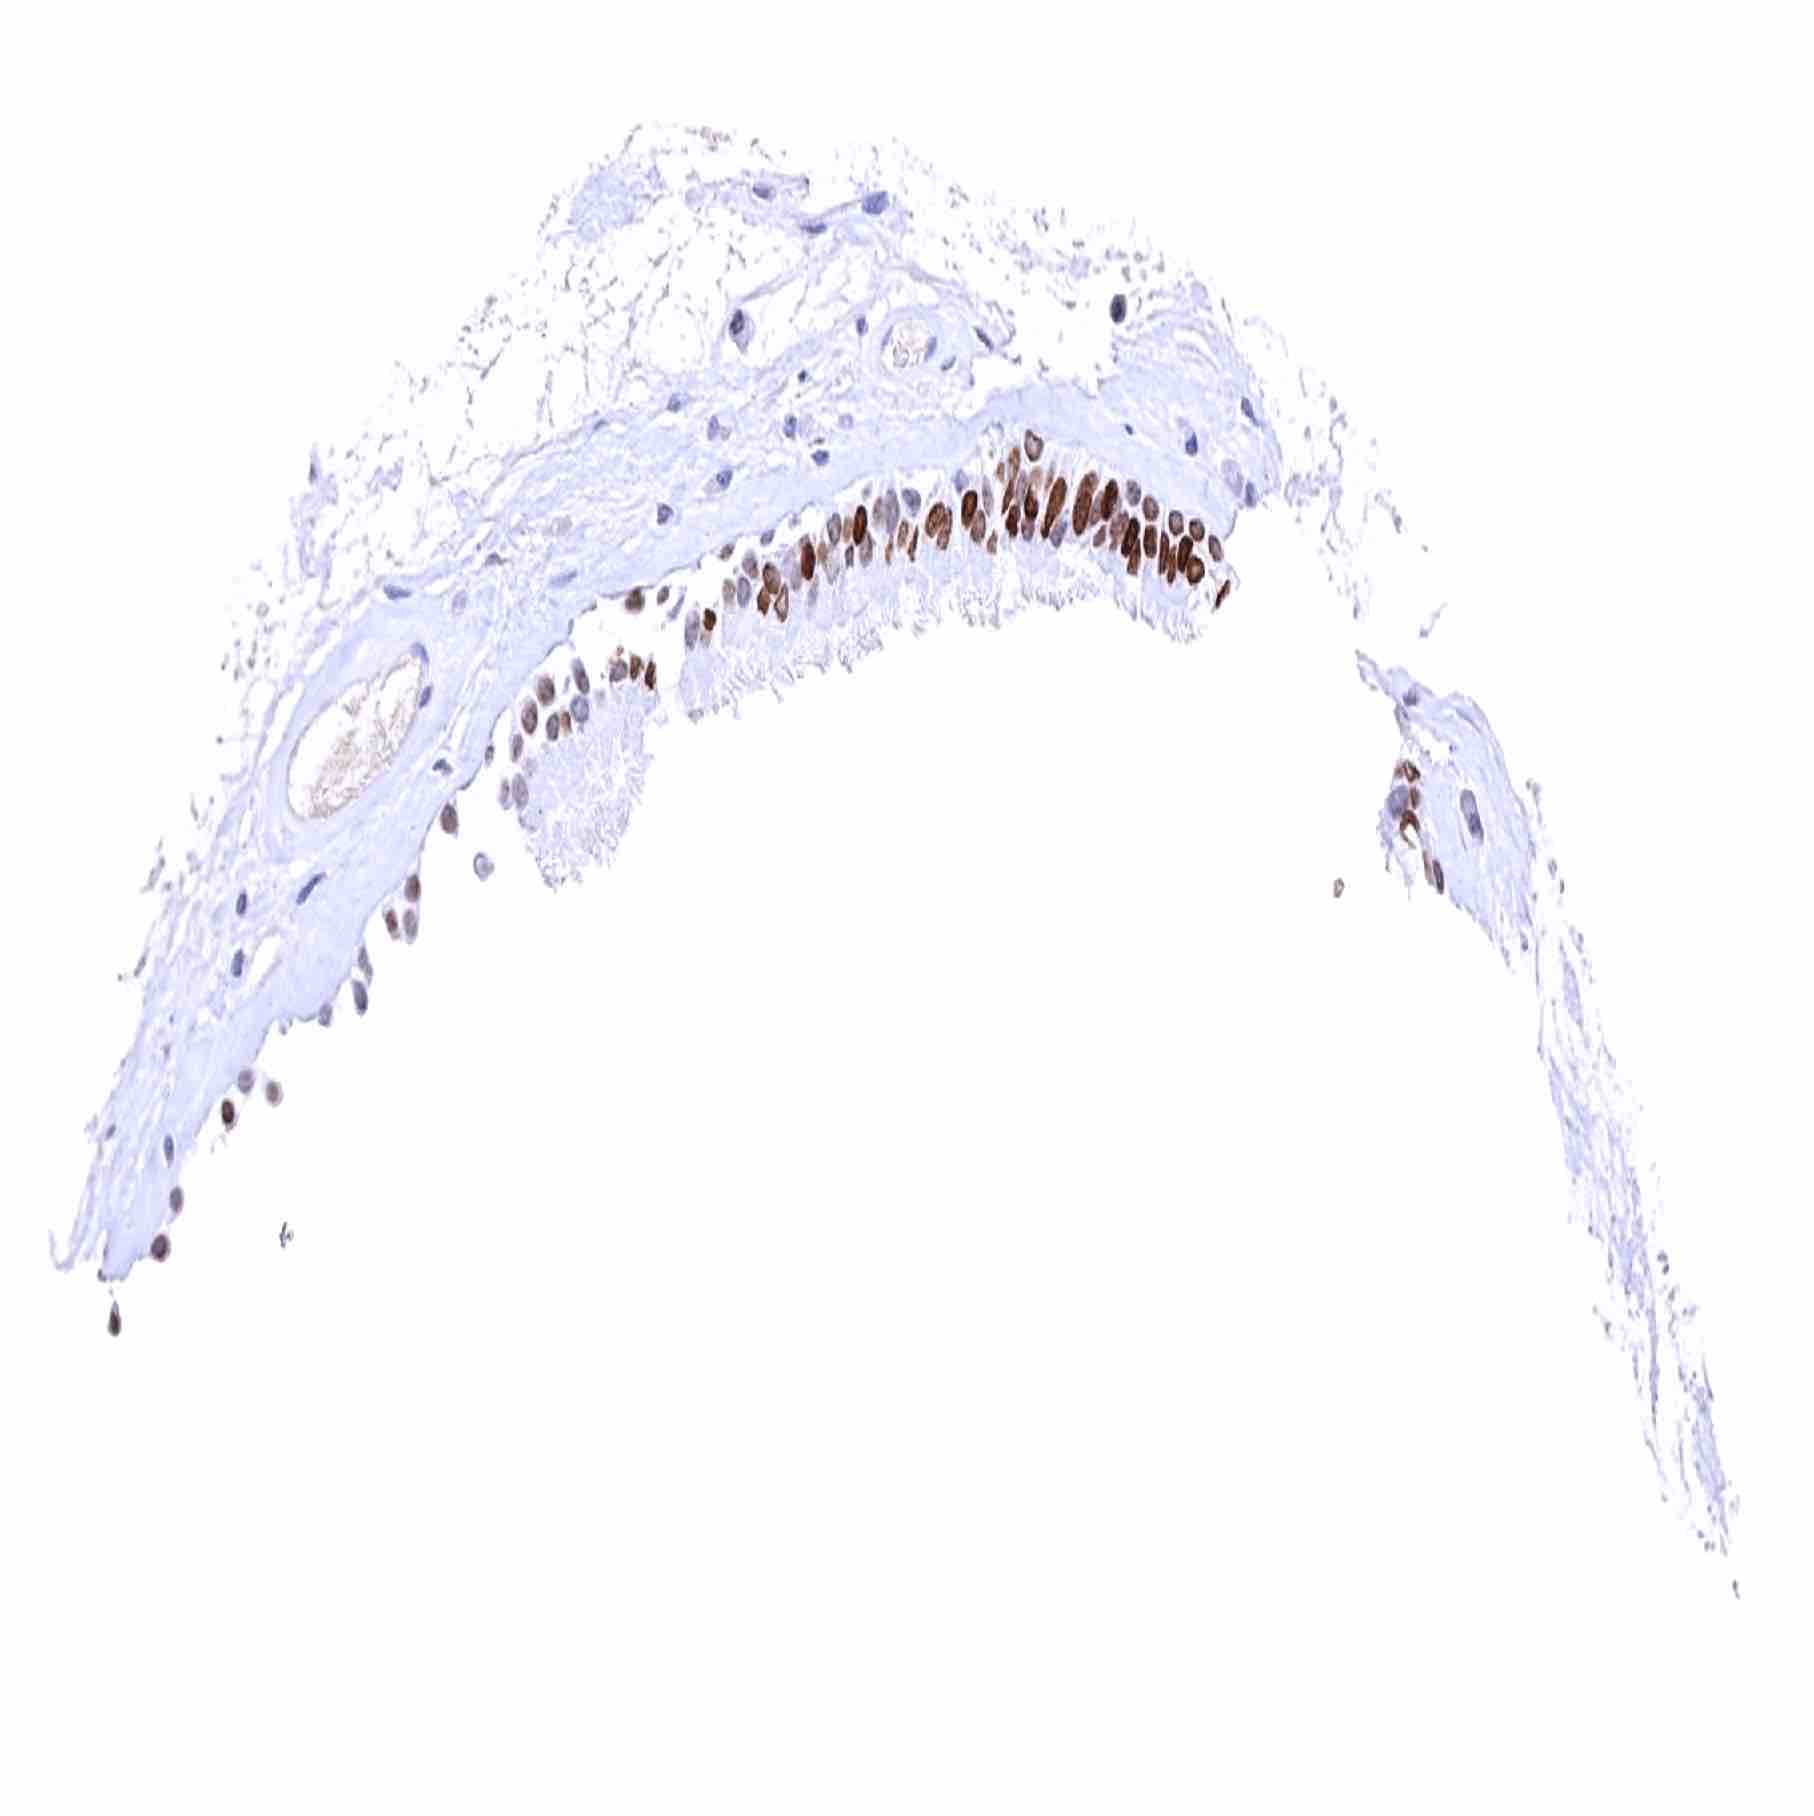

placenta (amnion and chorion) – Strong nuclear HMGA2 positivity of amnion and stroma cells while chorion cells are negative

Placenta, early – Strong nuclear HMGA2 staining of stroma cells. Trophoblast cells remain HMGA2 negative

Placenta, mature – Some nuclear HMGA2 staining of trophoblast cells in some samples. Stroma cells are HMGA2 negative